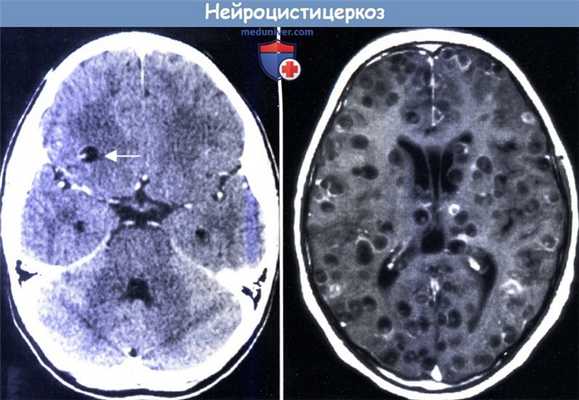

MPT: интрамуральные узелки одиночного цистицеркоза (слева, стрелка)

и множественные нейроцистицеркозные очаги (справа).

в) Нейроцистицеркоз. Нейроцистицеркоз (НЦЦ) наиболее распространенное гельминтозное заболевание ЦНС и основная проблема здравоохранения во многих развивающихся странах. Болезнь развивается в результате плохой санитарии, когда человек становится промежуточным хозяином в жизненном цикле Taenia solium, проглатывая яйца солитера. Инвазия инкапсулированной формой Т. solium может затем развиваться в пределах паренхимы мозга, базилярной цистерны или редко в спинном мозге, вызывая воспаление, отек и остаточную кальцификацию. Нейроцистицеркоз (НЦЦ) обычно проявляется у детей, когда цисты начинают отмирать и провоцировать воспаление. Среди признаков заболевания отмечают длительные очаговые/генерализованные припадки или иногда признаки повышенного внутричерепного давления, вторичного по отношению к цистицеркозному энцефалиту или гидроцефалии, вызванных кистевидными цистицерками в базилярной цистерне или желудочковой системе.

Диагностическим критерием служит выявление при сканировании мозга одиночного кольцевидного поражения с окружающим отеком или при обнаружении множественных поражений, некоторые из которых кальцифицированны. На МРТ можно обнаружить головку червя. Дифференциальная диагностика одиночных поражений от других единичных гранулем, таких как туберкулема, без биопсии затруднительна. Полезным может быть определение сывороточных антител против цистицерка, хотя в эндемичных районах исследование может привести к высокому уровню ложно-положительных результатов. Del Brutto et al. (2001) разработали набор диагностических критериев для помощи в установлении НЦЦ. Лечение альбендазолом (15 мг/кг/сут. в течение 8 дней) доказало свою эффективность, с добавлением стероидов в тяжелых случаях инвазии или при развитии побочных эффектов от лечения. Поскольку большинство пациентов обращается за медицинской помощью в результате отмирания цист, лечение уже не рекомендовалось; однако недавние исследования показали, что при использовании альбендазола уменьшается долговременный риск развития припадков (Garcia et al., 2004).